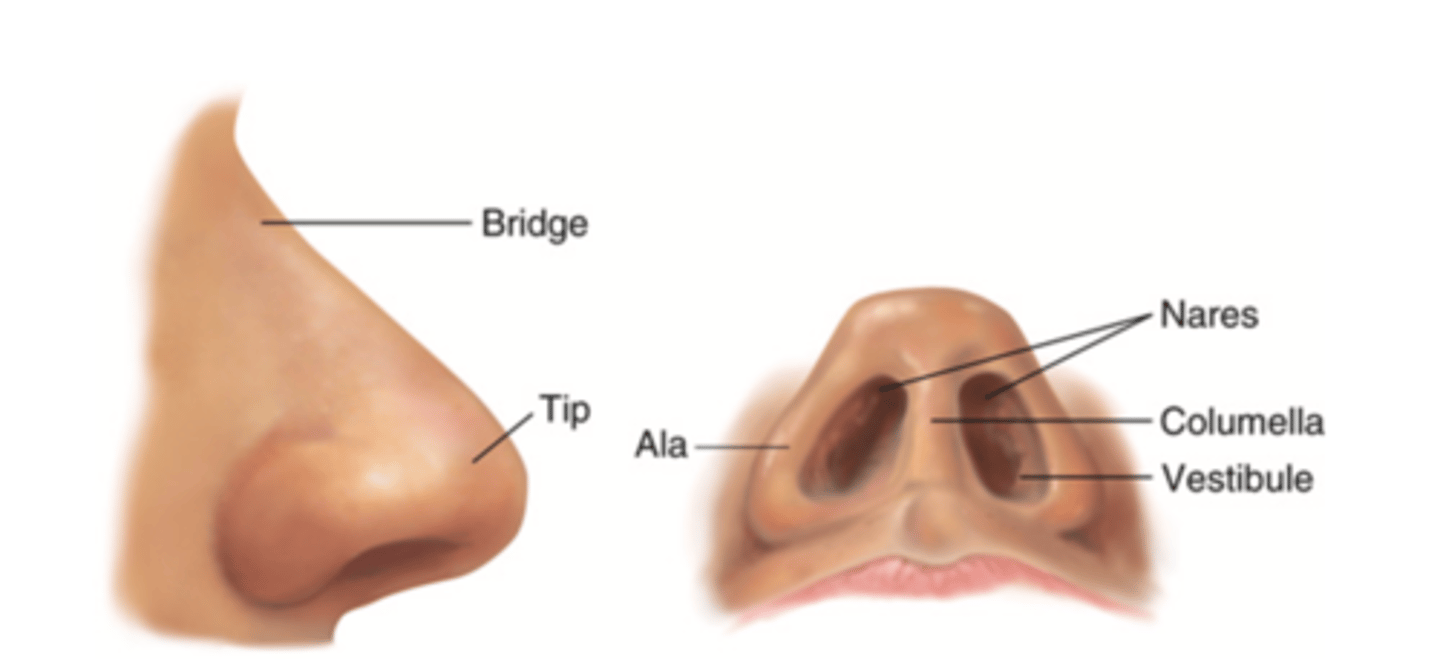

Nose

Organ of smell

Bridge

Tip

Ala

Nares

Columella

Vestibule